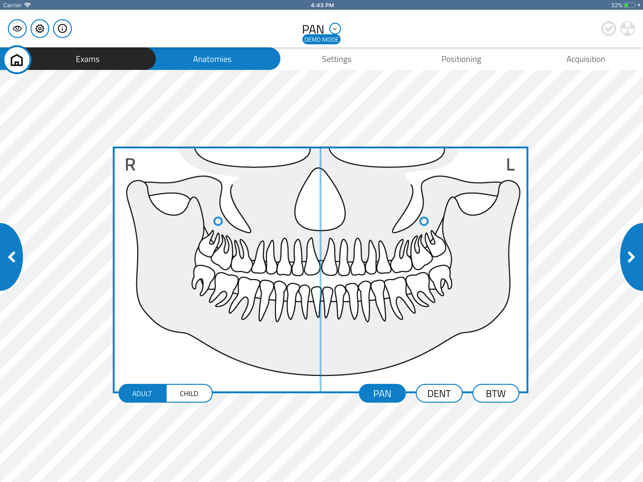

GiANO HR is a highly advanced dental equipment by NewTom, with panoramic, ceph and CBCT capabilities. NewTom Control Pad allows GiANO HR users to connect via Wi-Fi to the equipment, browse the diagnostic programs available, select an imaging modality and a region of interest before performing a radiographic examination.